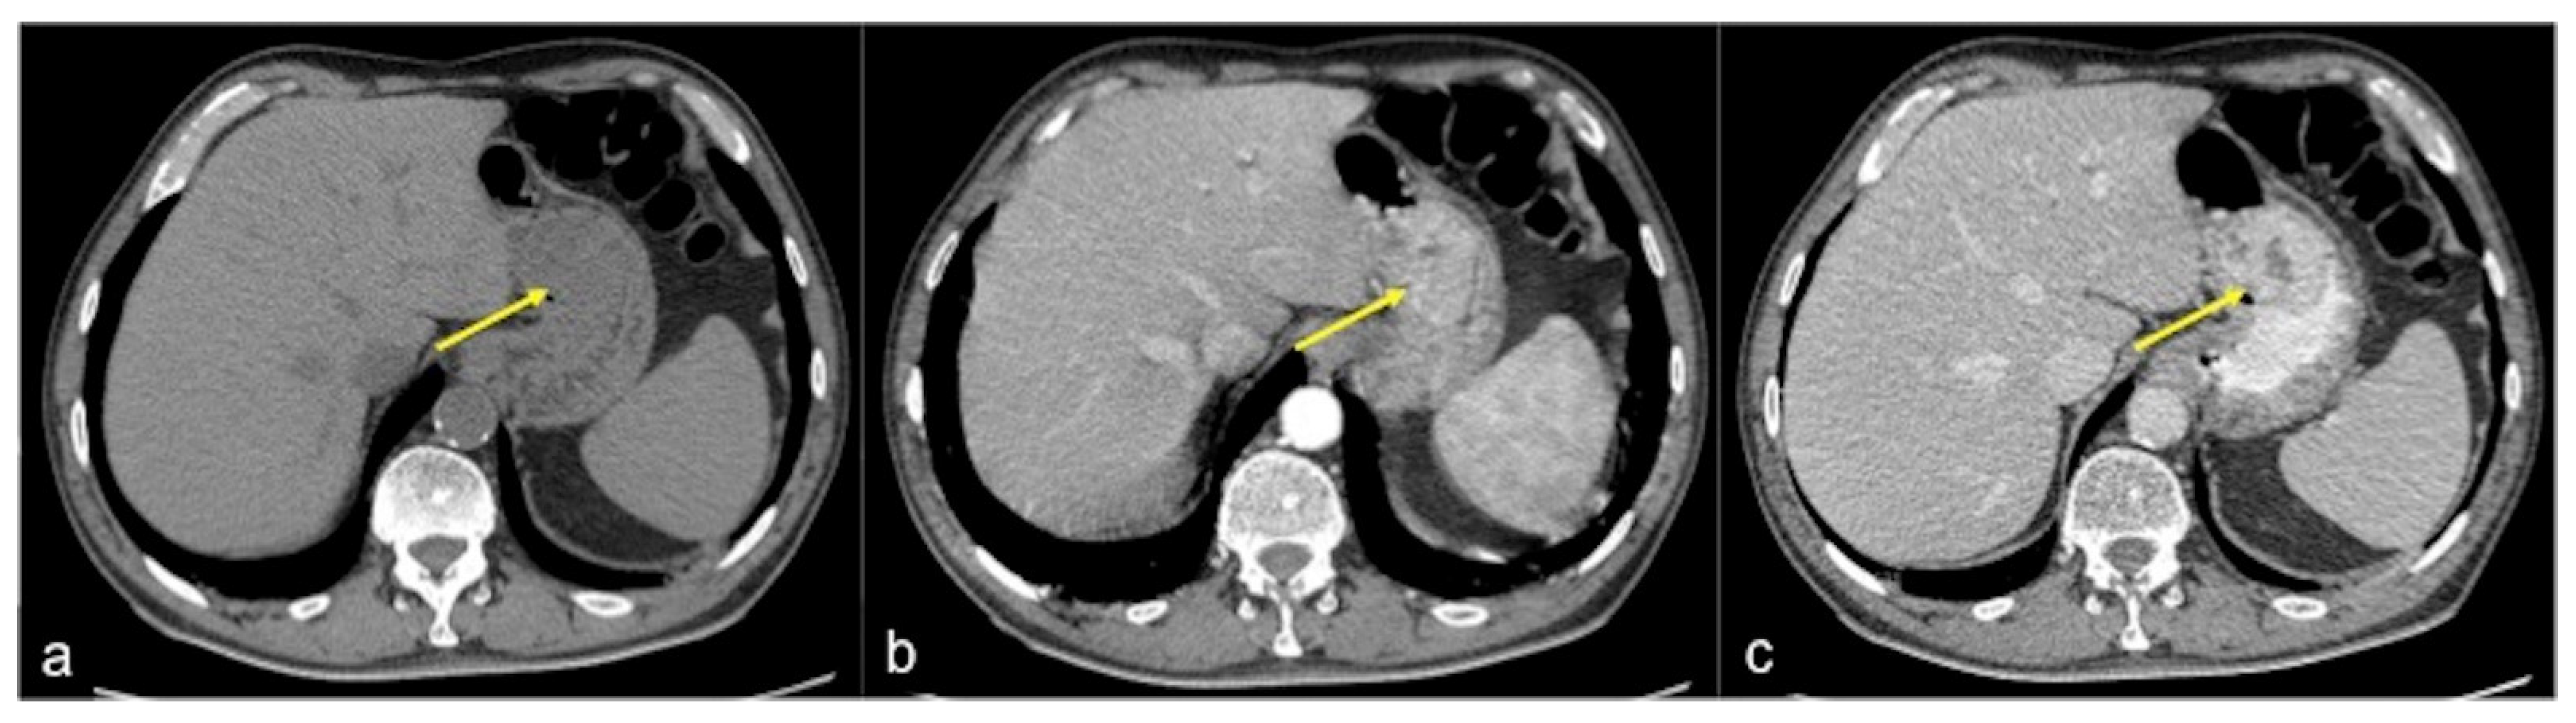

| Gastrointestinal Stromal Tumour (GIST) (Figure 26) | Asymptomatic or bleeding. | Soft tissue density mass with variable areas of necrosis. They are usually highly vascularised and the enhancement of the lesion may vary from homogeneous to peripheral and irregular depending on the lesion dimension and grade of malignancy. |